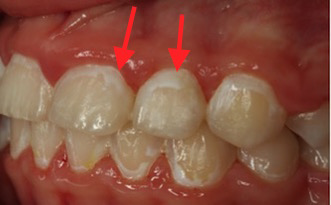

Cirka vart fjärde barn i Sverige behandlas med fast tandställning och upp till 50 % av dessa barn utvecklar så kallade ”White Spot Lesions” (WSL). Skadorna benämns WSL på grund av sitt oftast vitaktiga utseende, orsakat av ”urkalkning” av emaljen, och kan variera vad gäller antal drabbade ytor och utbredning på tanden (bild 1-2). Skadorna uppstår främst runt tandställningens fästen och kan upplevas som missprydande i och med att de ofta återfinns på framtänderna. Skadorna, som har en begränsad förmåga att spontant läka ut, kan liknas vid ett ärr som försämrar det slutgiltiga behandlingsresultatet.